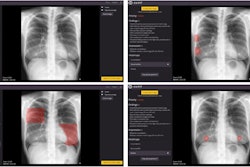

While AI continues to show its potential in aiding radiologists and other clinicians to diagnose patients, systematic bias persists as a barrier to the technology’s widespread use by reducing diagnostic accuracy. Recent regulatory guidance has called for AI models to include explanations to help lessen errors made by models. However, the researchers noted a lack of data showing the effectiveness of this strategy.

Jabbour and co-authors studied the impact of systematically biased AI on clinician diagnostic accuracy, as well as whether image-based AI model explanations could decrease model errors. The multicenter study included hospitals in 13 U.S. states, using a survey administered between April 2022 and January 2023.

The team showed 572 participating clinicians nine clinical vignettes of hospitalized patients with acute respiratory failure. These included symptoms, physical examinations, laboratory results, and chest radiographs. From there, the clinicians determined the likelihood of pneumonia, heart failure, or chronic obstructive pulmonary disease as the underlying cause in each case.